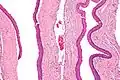

Odontogenic keratocysts have a diagnostic histological appearance. Under the microscope, OKCs vaguely resemble keratinized squamous epithelium;[15] however, they lack rete ridges and often have an artifactual separation from their basement membrane.[2]

The fibrous wall of the cyst is usually thin and uninflamed. The epithelial lining is thin with even thickness and parakeratinised with columnar cells in the basal layer which have focal reverse polarisation (nuclei are on the opposite pole of the cell).[13] The basal cells are an indication of the odontogenic origin as they resemble pre-ameloblasts. The epithelium can separate from the wall, resulting in islands of epithelium. These can go on to form 'satellite' or 'daughter' cysts, leading to an overall multilocular cyst.[10] Presence of daughter cysts is particularly seen in those with NBCCS.[13] Inflamed cysts show hyperplastic epithelium which is no longer characteristic of OKCs and can have resemblance to radicular cysts instead. Due to areas of focal inflammation, a larger biopsy is required for correct diagnosis of odontogenic keratocysts.[10]